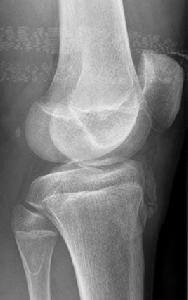

1.局部軟組織腫脹為重要的基本徵像,尤以髕韌帶的增大或增厚為著,以後肌腱可產生繼發性鈣化或骨化。

2.脛骨結節骨骺不規則增大,密度不勻,有節裂或邊緣光滑的游離骨塊。結合臨床,本病診斷不難,但常需與健側對照觀察。